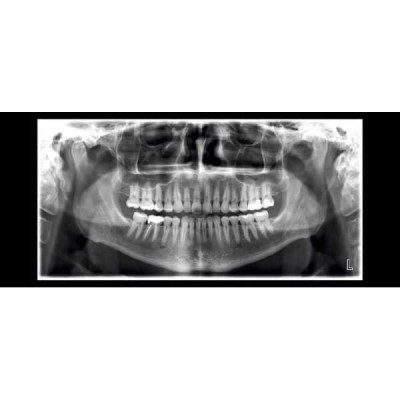

Ортопантомограф Planmeca ProMax 2D Scara3 рентгенологическая установка принципиально новой конструкции, предлагающая самый широкий спектр программ для 2D визуализации зубо-челюстной системы и лор органов. Аппарат позволяет использовать предустановленные программы или откорректировать параметры экспозиции, чтобы минимизировать дозу облучения пациентов.

Основные панорамные программы:

- Стандартная панорама взрослого

- Стандартная панорама ребенка